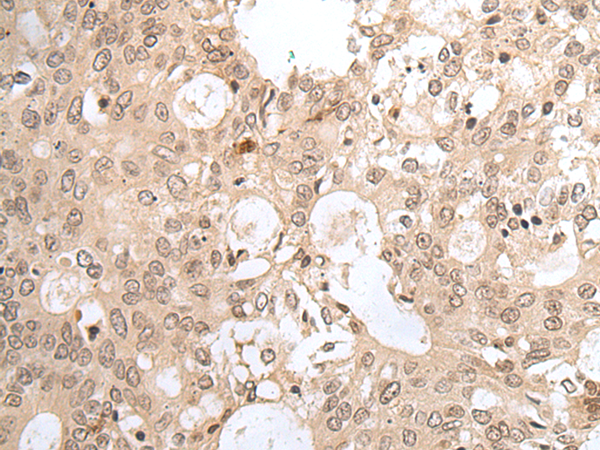

IHC positive control:

Human colorectal cancer and human tonsil

IHC Recommend dilution:

25-100